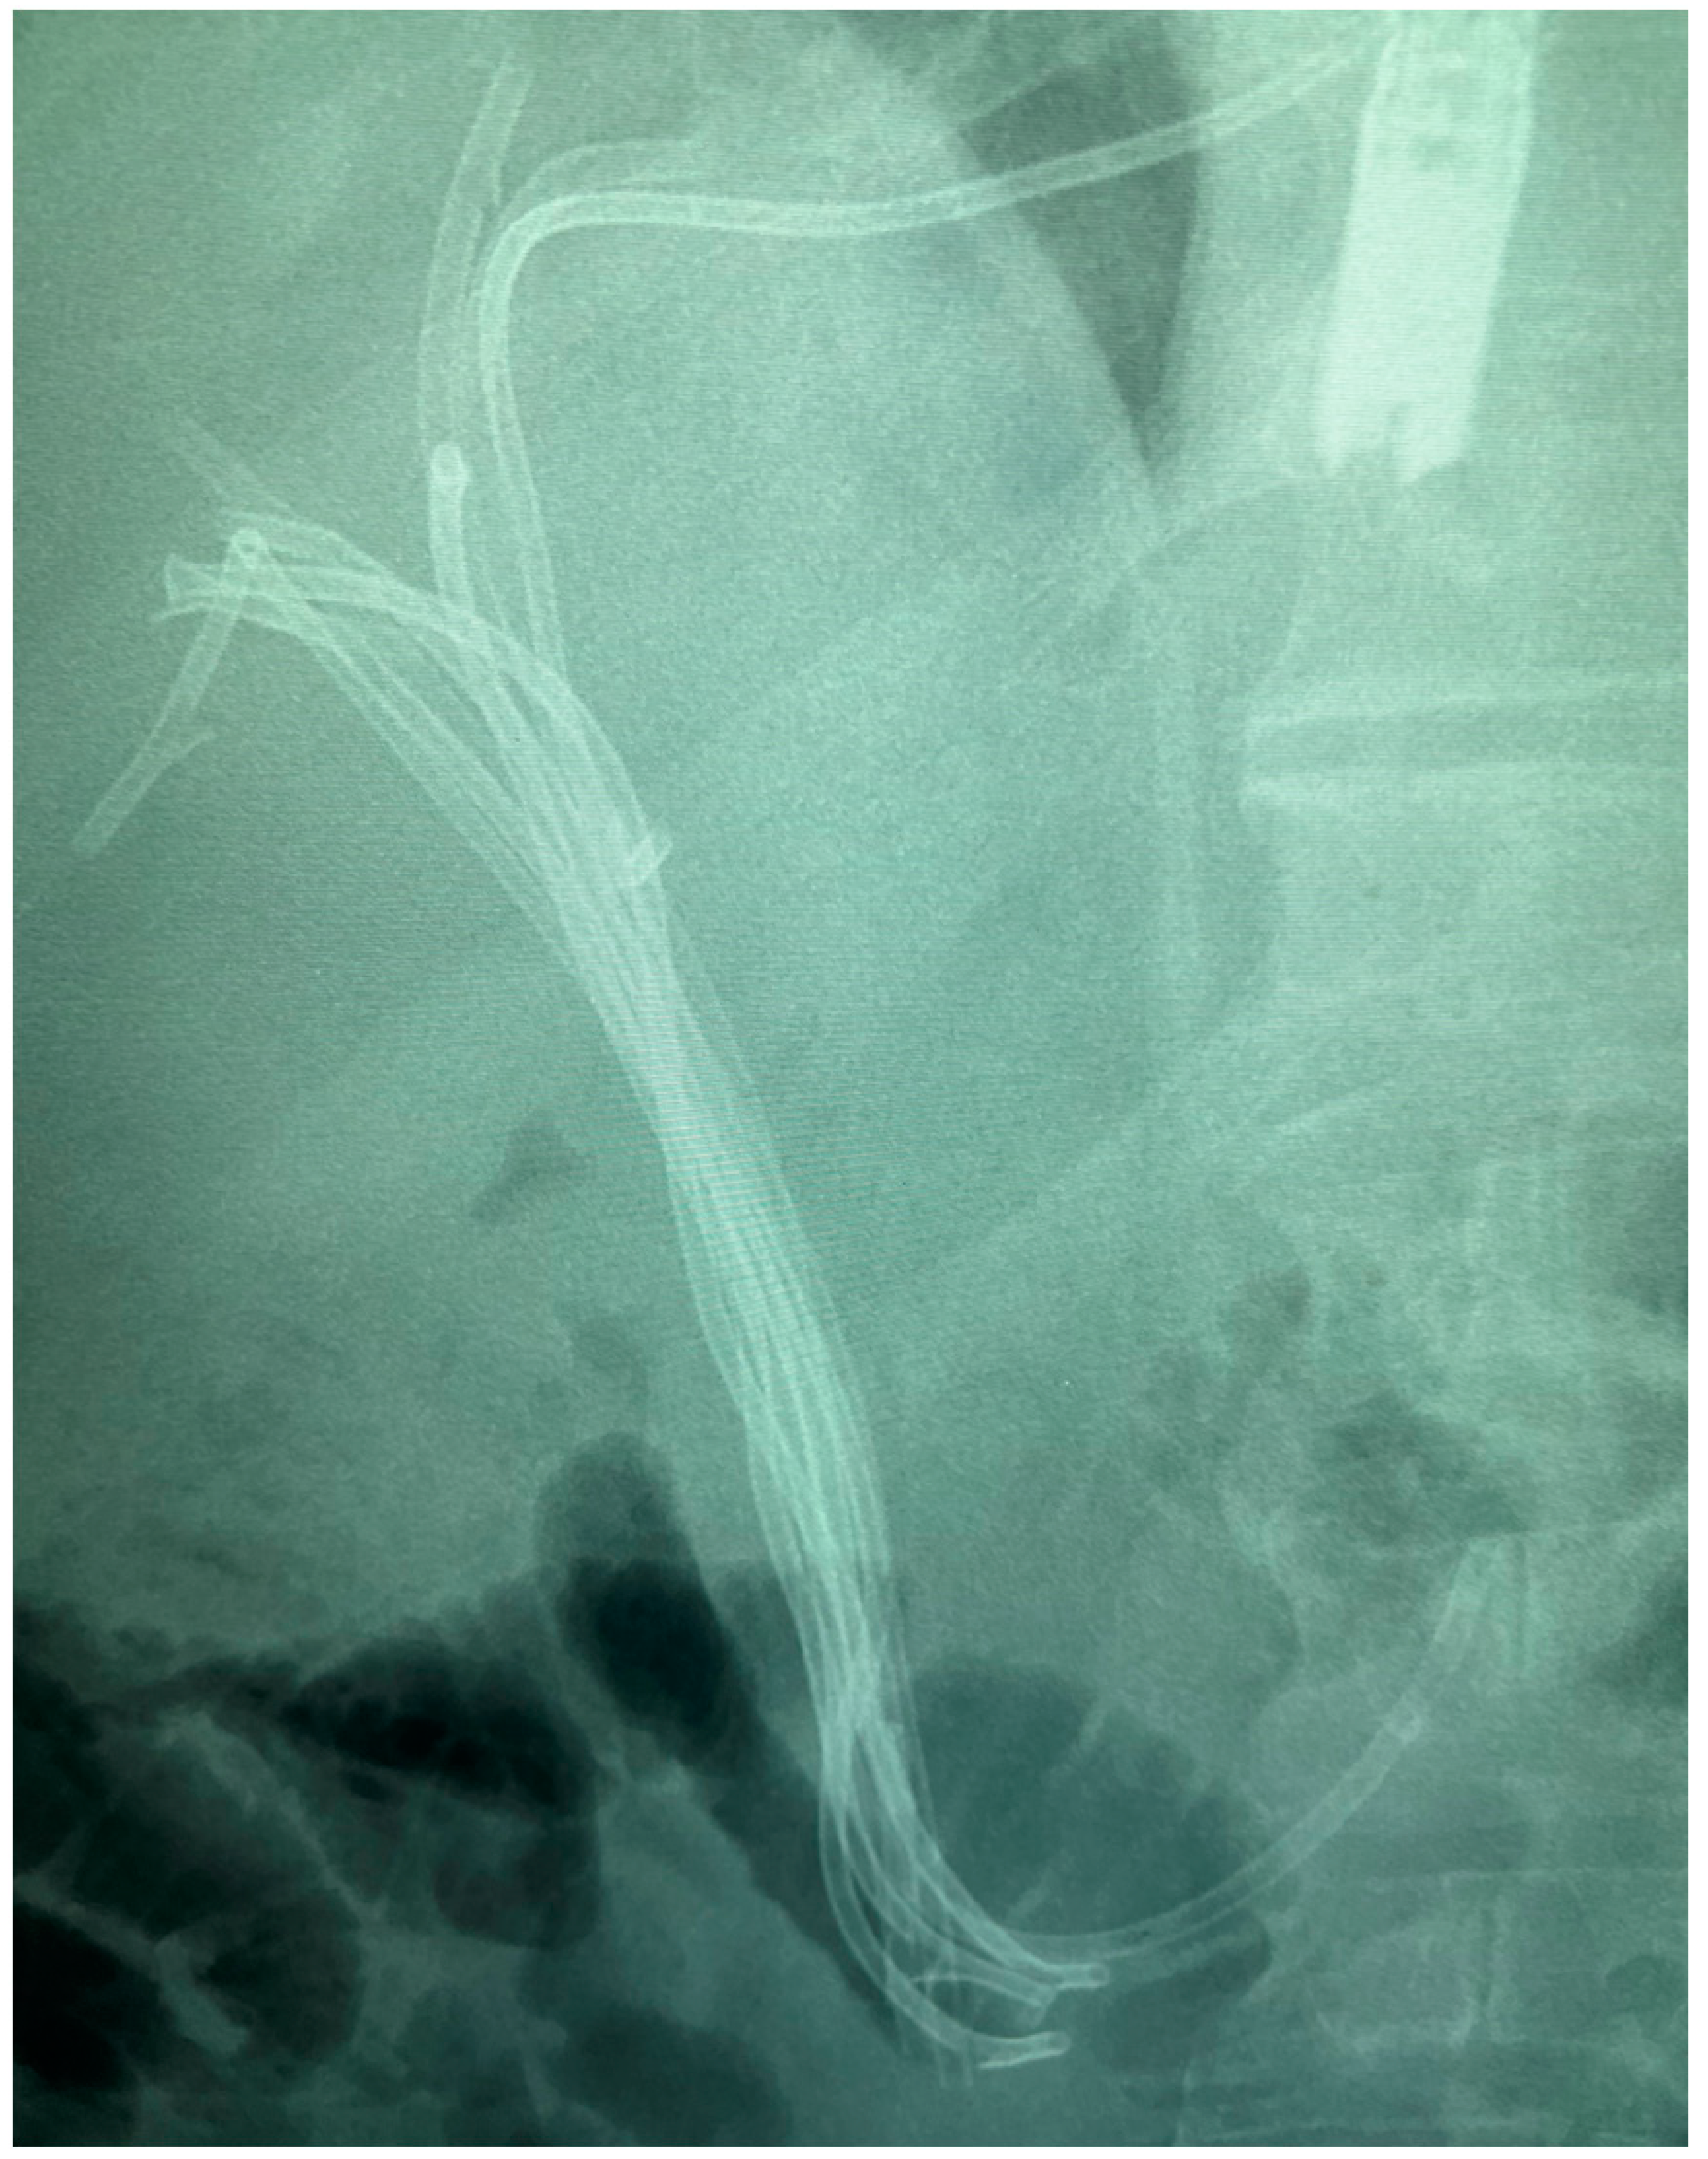

7.1.2. Endoscopic Nasobiliary Drainage (ENDB)

7.1.3. EUS-Guided Biliary Drainage (EUS-BD)

- Maeda, T.; Ebata, T.; Yokoyama, Y.; Mizuno, T.; Yamaguchi, J.; Onoe, S.; Watanabe, N.; Kawashima, H.; Nagino, M. Preoperative course of patients undergoing endoscopic nasobiliary drainage during the management of resectable perihilar cholangiocarcinoma. J. Hepatobiliary Pancreat. Sci. 2019, 26, 341–347. [Google Scholar] [CrossRef]

- Kawashima, H.; Itoh, A.; Ohno, E.; Itoh, Y.; Ebata, T.; Nagino, M.; Goto, H.; Hirooka, Y. Preoperative endoscopic nasobiliary drainage in 164 consecutive patients with suspected perihilar cholangiocarcinoma: A retrospective study of efficacy and risk factors related to complications. Ann. Surg. 2013, 257, 121–127. [Google Scholar] [CrossRef]